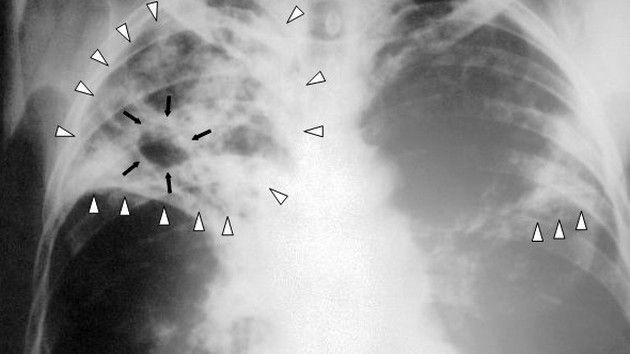

За десета поредна година трайно намаляват болните от туберкулоза в страната

Над 78% от регистрираните пациенти са с туберкулоза на белия дроб. Над 59% от пациентите с белодробна туберкулоза отделят туберкулозни бацили и крият риск за околните контактни лица. През годините се запазва тенденция броят на мъжете да е над два пъти по-голям от броя на жените.